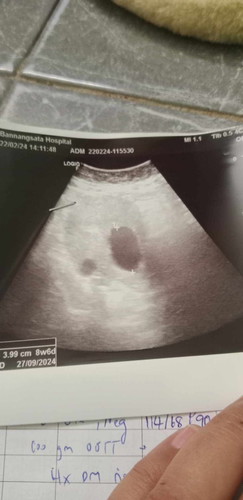

ถามแม่น่ะคะ ทำไมในใบซาวด์ขึ้น 8w6dค่ะ อันจริง11w3dค่ะ ขอบคุณค่ะ

ไปคลีนิกแล้วค่ะ ไม่เจอเหมือนกันค่ะ หมอบอกถึงครรภ์ใหญ่9เซน ค่ะ